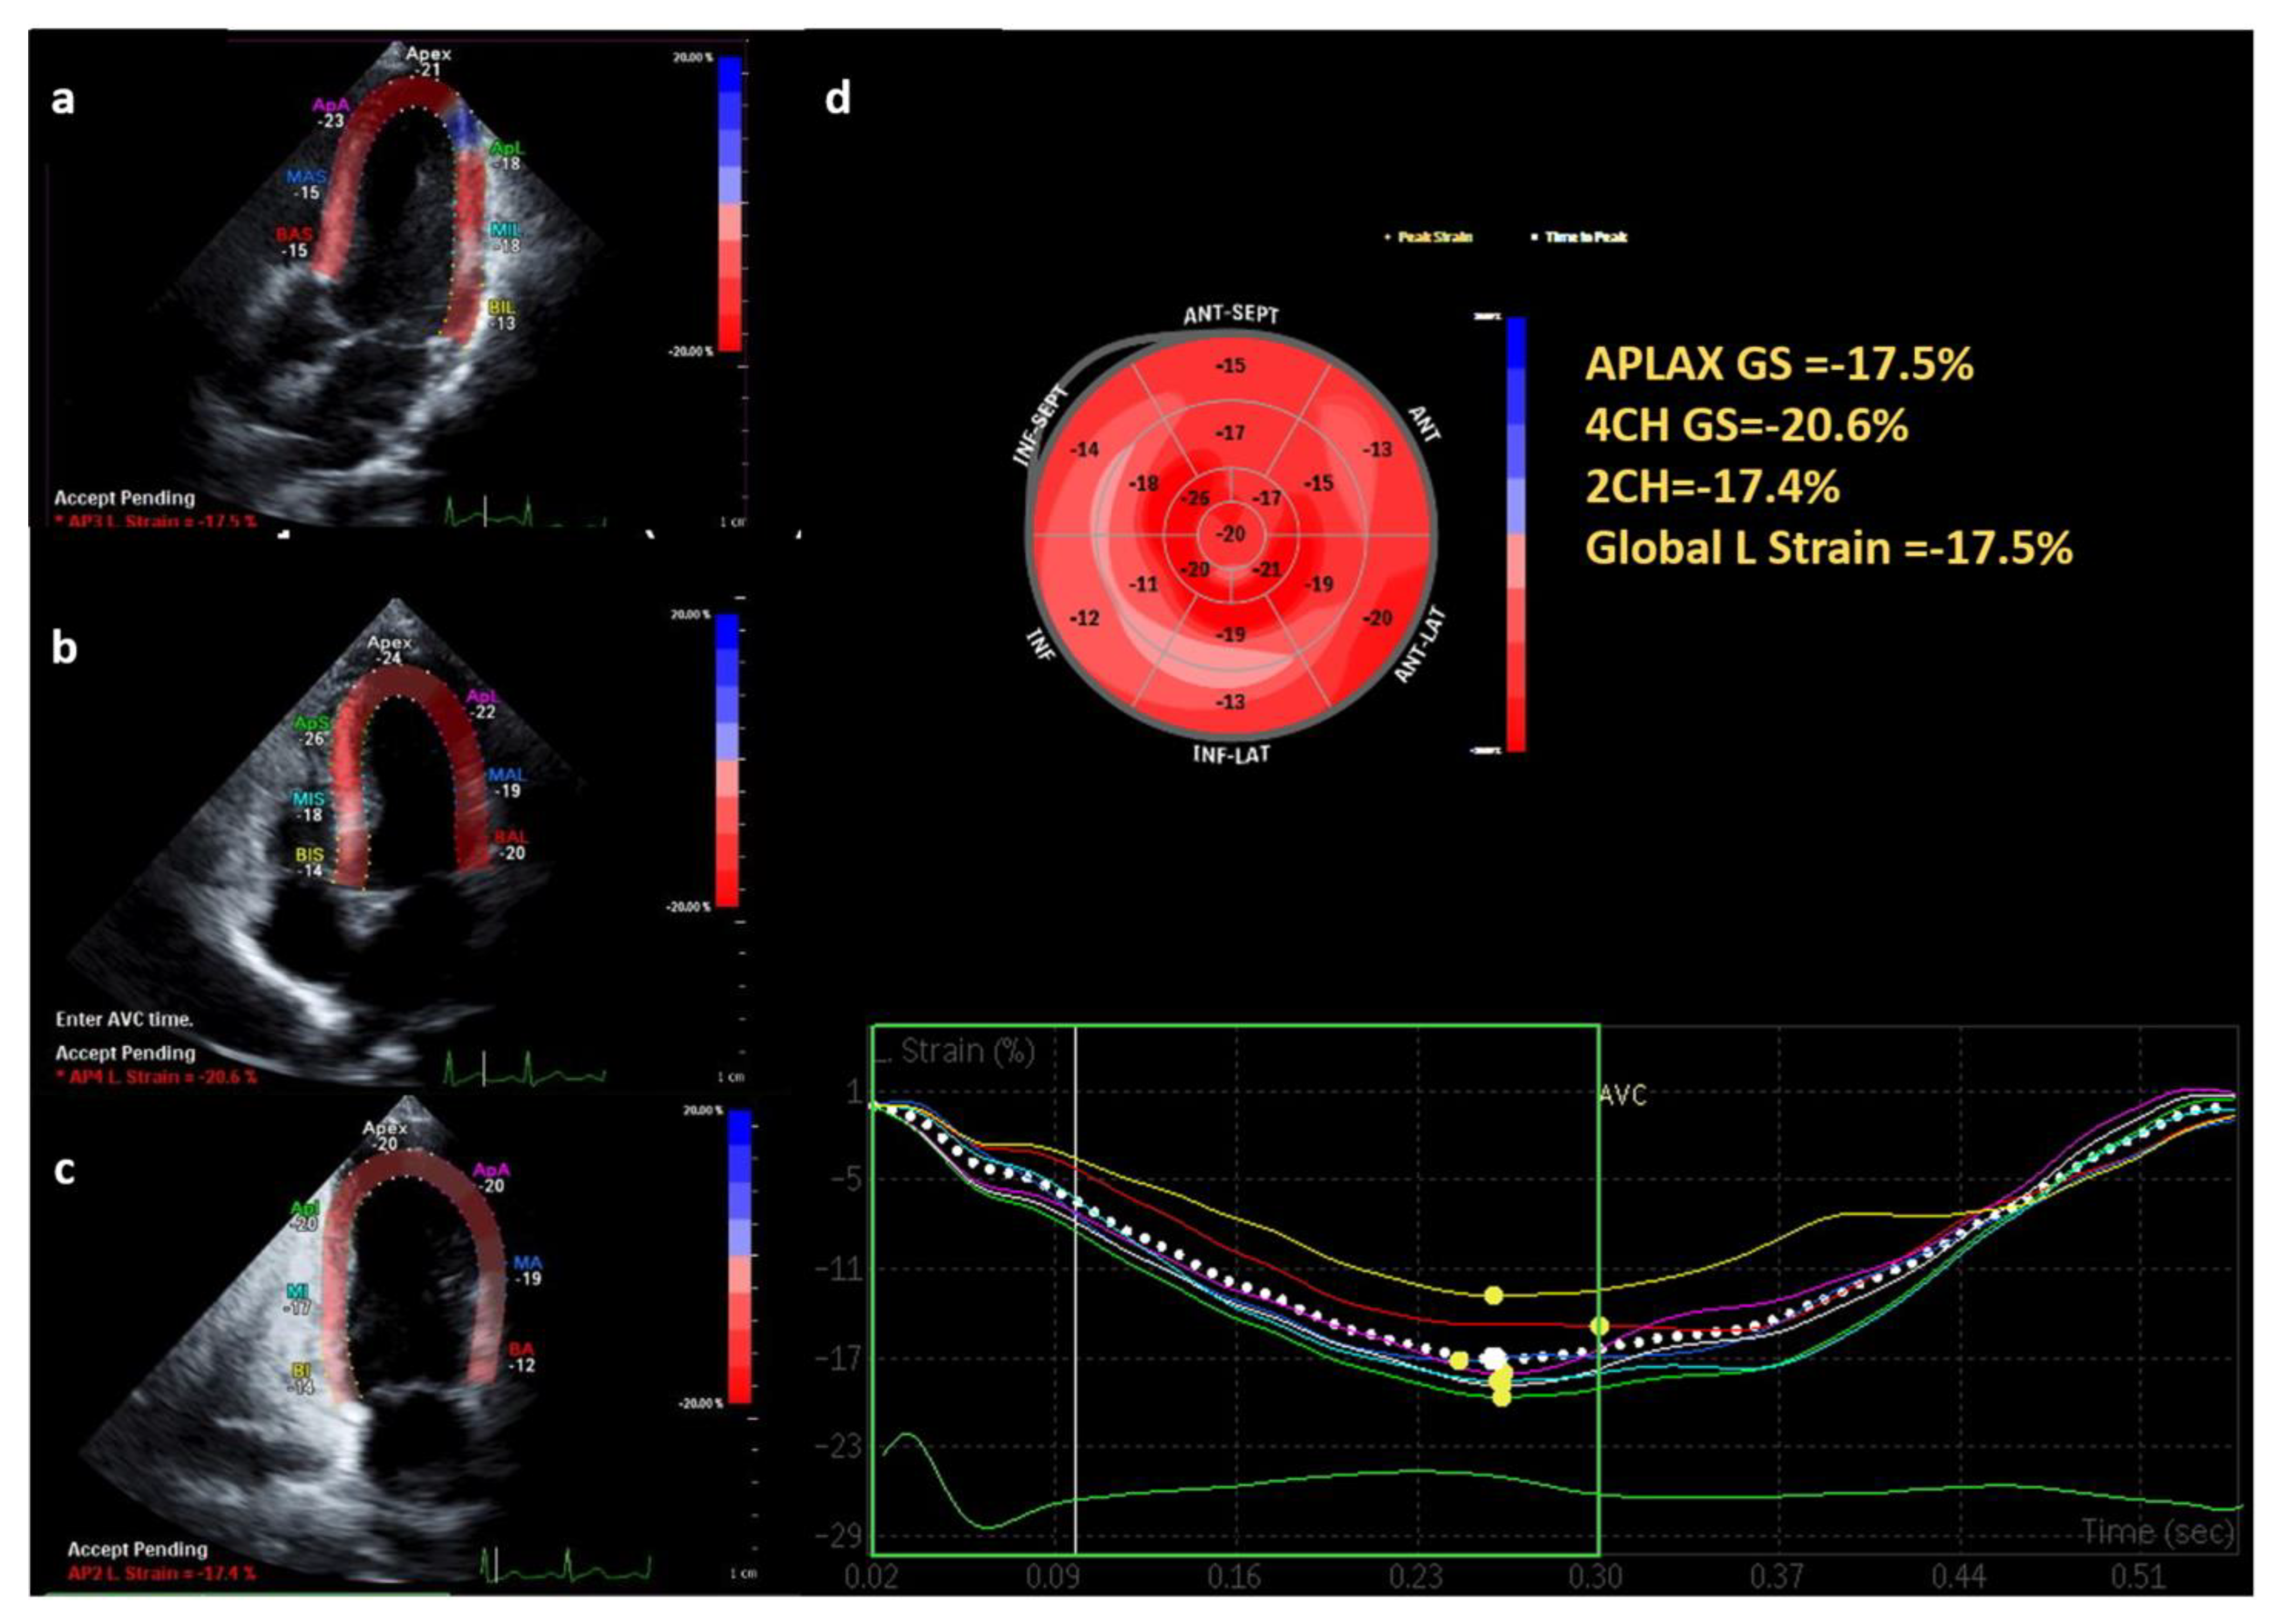

2.2. Echocardiography Analysis